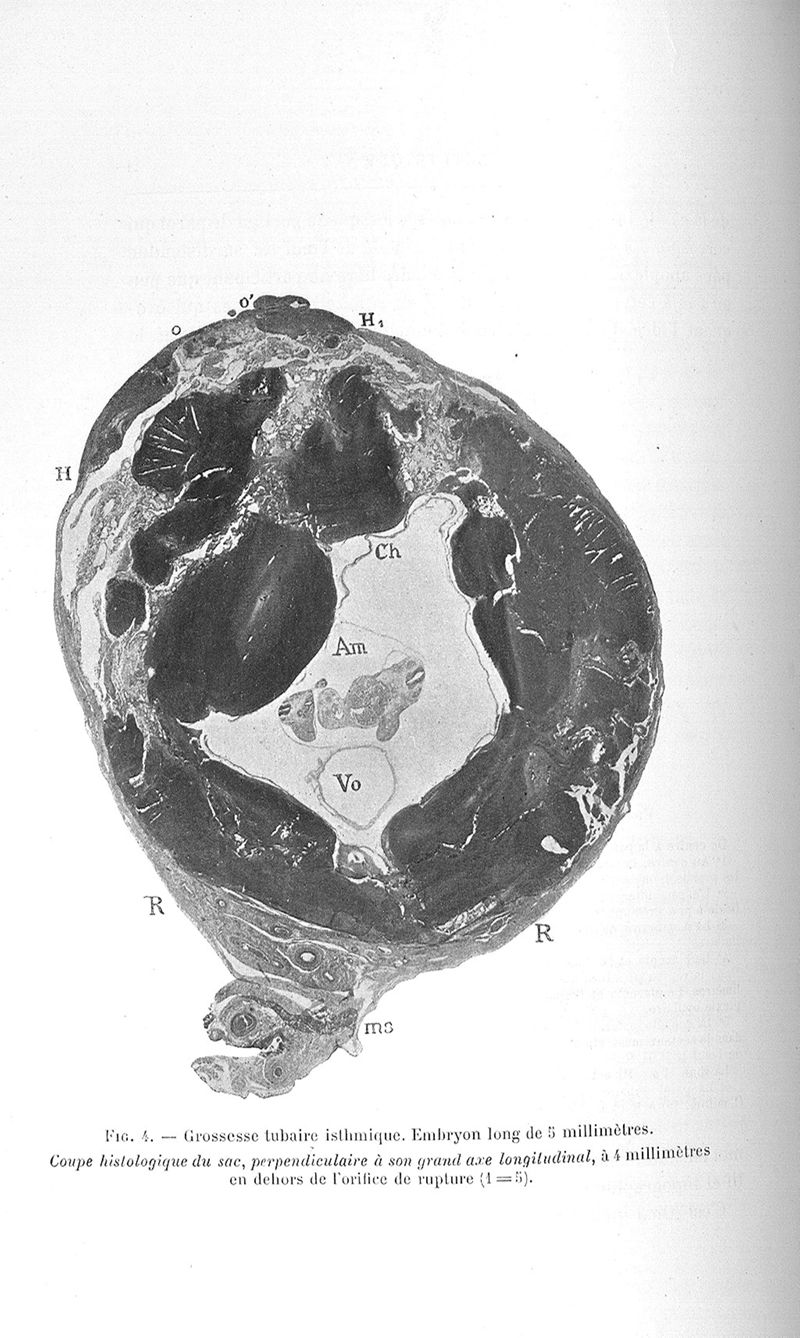

Couvelaire, Alexandre Adrien M..

Exposé des travaux

Paris, G. Steinheil, 1904.